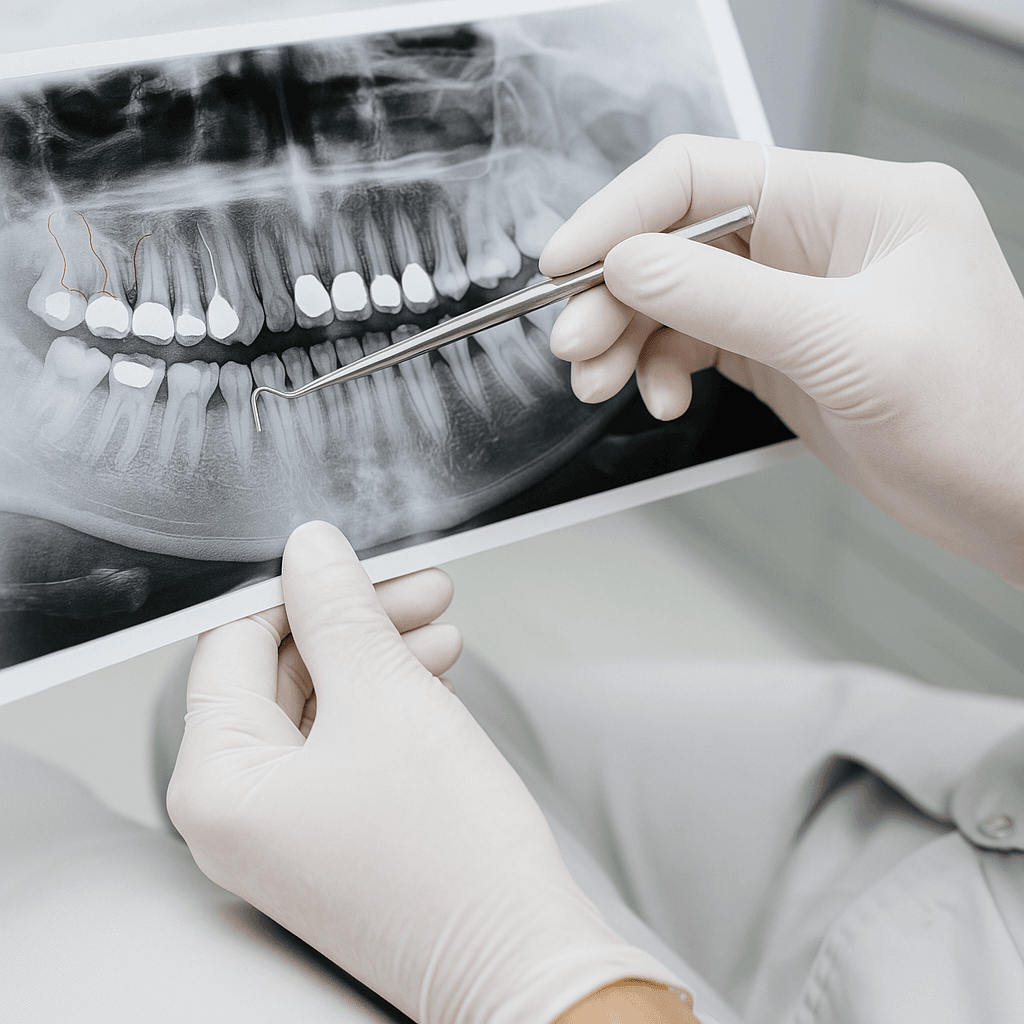

- • Dzięki tomografii CBCT możliwe jest uzyskanie szczegółowego obrazu struktur anatomicznych, co pozwala na precyzyjne zaplanowanie położenia implantu i bezpieczne przeprowadzenie zabiegu.